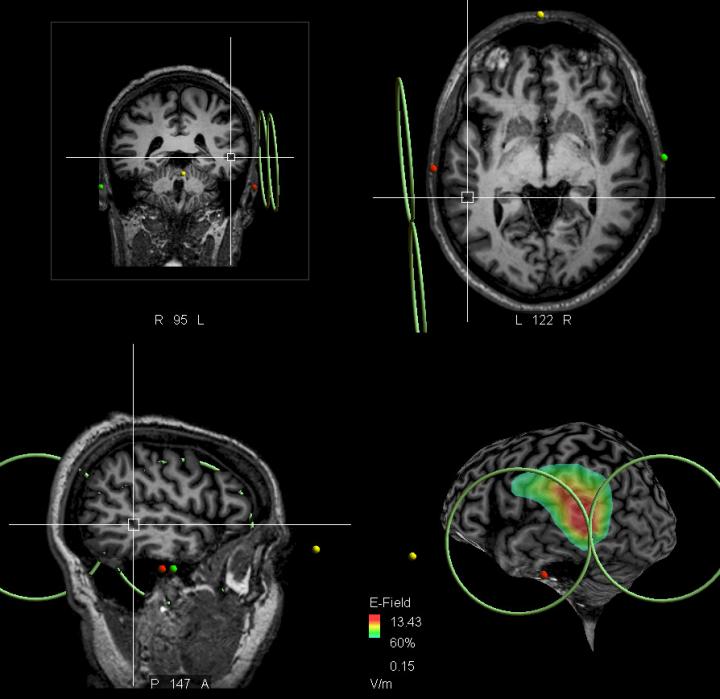

The French research team worked with 26 patients who received active TMS treatment, and 33 as a control group, who received sham (placebo) treatment. The researchers interviewed the patients using a standard protocol - the Auditory Hallucinations Rating Scale - which revealed most of the characteristic features of the voices which they were hearing. The treated patients received a series of 20 Hz high-frequency magnetic pulses over 2 sessions a day for 2 days. Using magnetic resonance imaging (MRI), the pulses were targeted at a specific brain area in the temporal lobe, which is associated with language (the exact area is the crossing of the projection of the ascending branch of the left lateral sulcus and the left superior temporal sulcus)